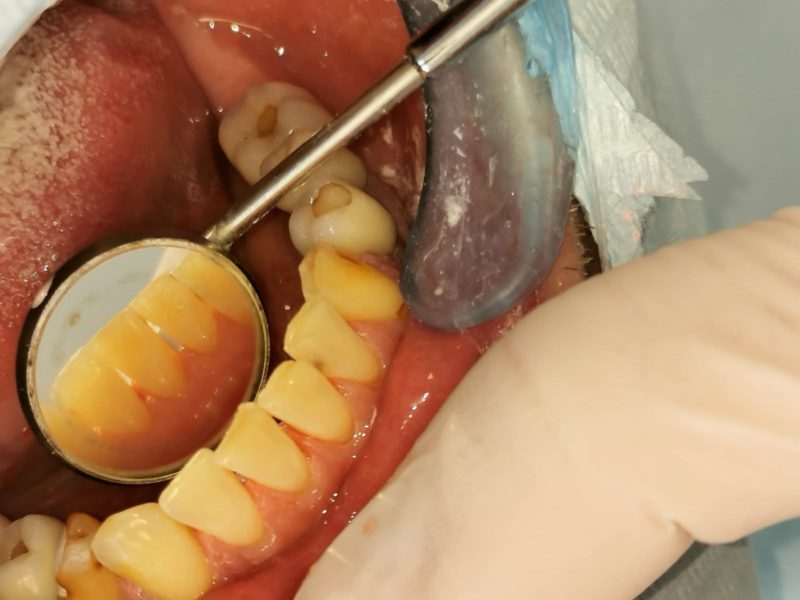

Specialiais instrumentais ir ultragarsiniu skaleriu pašaliname ant dantų susikaupusius akmenis. Su smėliasrove ir perlų soda nuvalome tabako, arbatos, kavos, vyno apnašas.

Dantų poliravimas su soda, E-FLOW technologija leidžia pašalinti atsiradusias pigmentines dėmes!

- Kruopšti burnos higienos specialistė: Ashbourne Dental & Medical klinikoje burnos higienos specialist Greta Samalionytė itin daug dėmesio skiria paciento būklės įvertinimui ir procedūrą atlieka pasitelkdama inovatyvų skalerį. Tinkamai ir laiku atlikta profesionali dantų apnašų šalinimo procedūra yra geriausia dantų ir dantenų ligų prevencija.

- Inovatyvios technologijos: Ashbourne Dental & Medical klinikoje burnos higienos procedūra atliekama inovatyviu ir saugiu Piezo Ultrasonic skaleriu, kurio pagalba apnašos ir akmenys pašalinami gerokai greičiau ir paprasčiau, o procedūra – komfortiškesnė. Kai kuriais atvejais, atsižvelgiant į paciento būklę, kartu su skaleriu gali būti naudojamas ir rankinis instrumentų rinkinys.